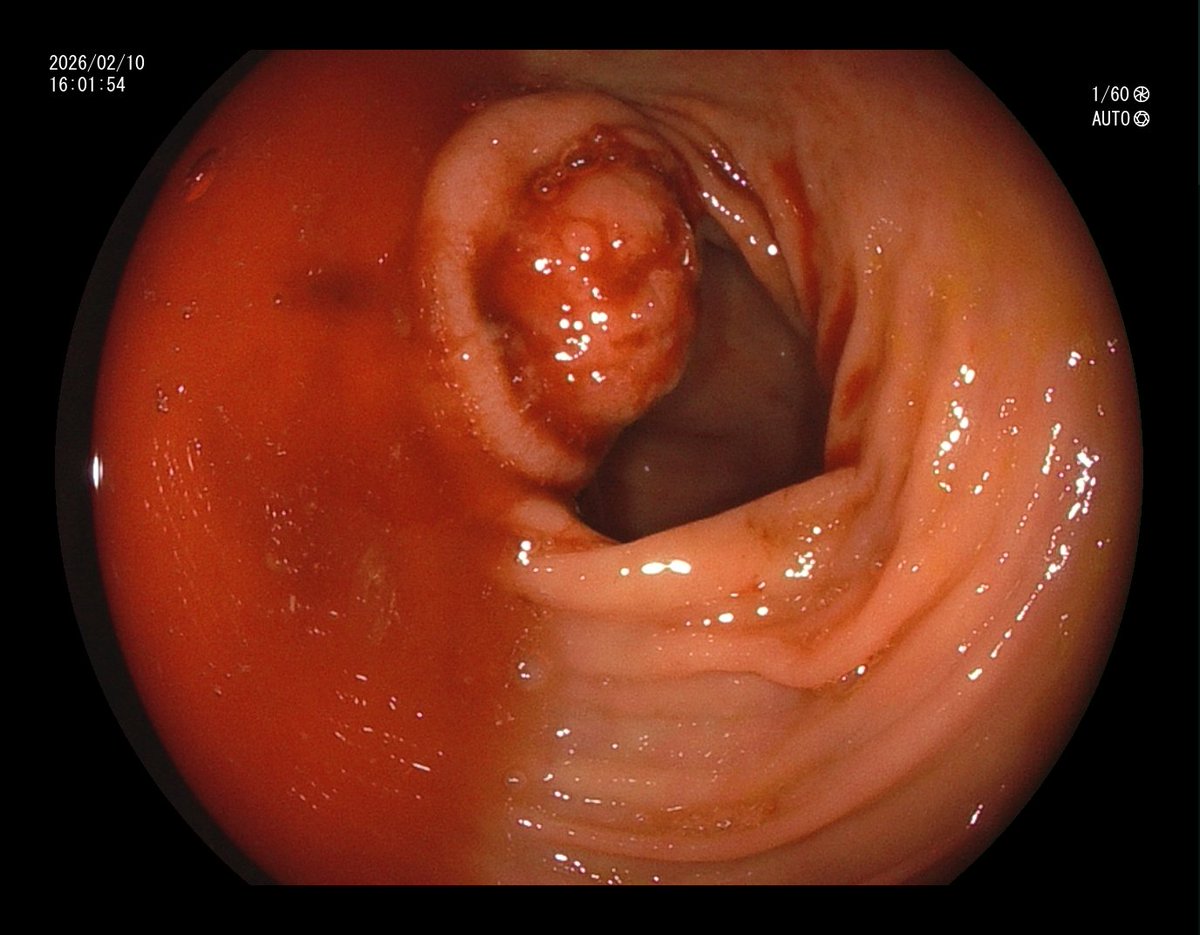

1. Antrum, low grade dysplasia. Removed via ESD. Specimen 43x32mm / dysplasia 20x13mm. R0